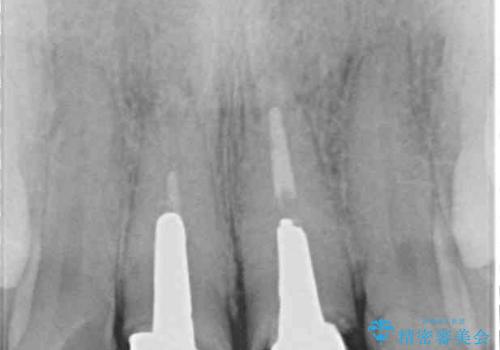

- 前歯のクラウンが着色により不自然な色となっていることを気にして来院された患者様です。

クラウンと歯の縁も合っておらず、汚れが溜まりやすい環境であったため、前歯2歯のクラウンをオールセラミッククラウンにて再補綴することとしました。